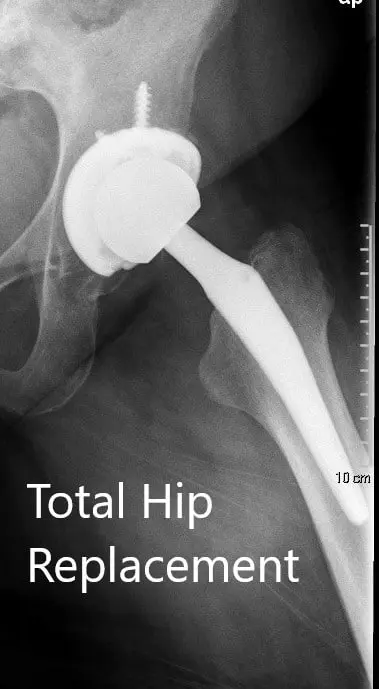

OPERACIÓN: Artroplastia total de cadera izquierda usando cabeza femoral cerámica de 36 mm más 5 con un sistema de tallo de cuello de 127 grados tamaño 5 con un agujero de racimo de concha acetabular de 54 mm con inserto de polietileno con dos tornillos.

Radiografía postoperatoria que muestra la vista AP de la pelvis y la vista lateral de la cadera izquierda.